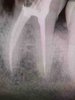

• Работа с дентальным рентгеном, радиовизиографом

Анализ прицельных рентген-снимков, ОПТГ, КТ.

Проведение и анализ снимков на визиографе и рентген-аппарате.